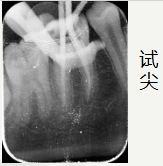

依次使用

欧罗德卡 机用锉混号 的

开口锉15/08疏通锉15103过渡锉20/05成型锉25/06